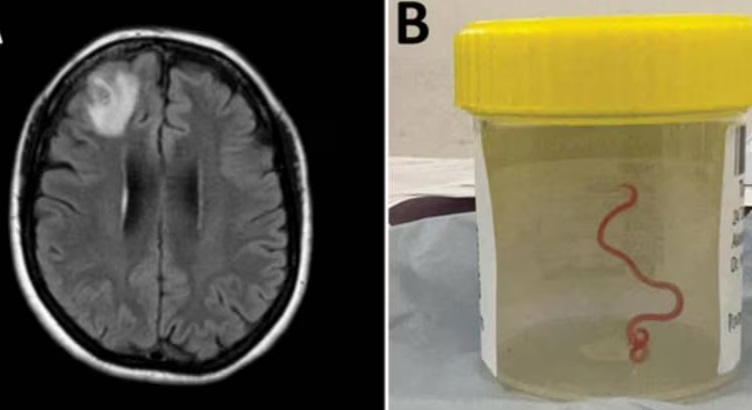

The Ophidascaris robertsi roundworm was pulled from the patient after brain surgery — still alive and wriggling. It is suspected larvae, or juveniles, were also present in other organs in the woman’s body, including the lungs and liver.

“This is the first-ever human case of Ophidascaris to be described in the world,” said Sanjaya Senanayake, leading ANU and Canberra Hospital infectious disease expert in a paper published in the journal Emerging infectious diseases.

“To our knowledge, this is also the first case to involve the brain of any mammalian species, human or otherwise. Normally the larvae from the roundworm are found in small mammals and marsupials, which are eaten by the python, allowing the life cycle to complete itself in the snake,” Senanayake added.